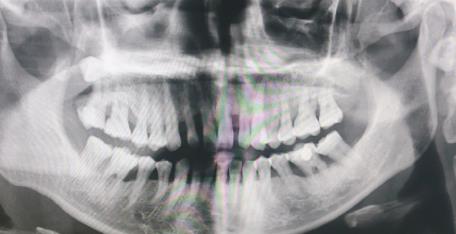

1、全景片:通常就是可以拍出口腔內(nei) 所有的牙齒情況的,通常從(cong) 全景片可以看到有無智齒,牙槽骨情況好不好,有無多生牙、有無假牙等修複體(ti) ,有多少顆蛀牙等。價(jia) 格一般在一兩(liang) 百元左右。如下圖:

有兩(liang) 顆智齒的全景片